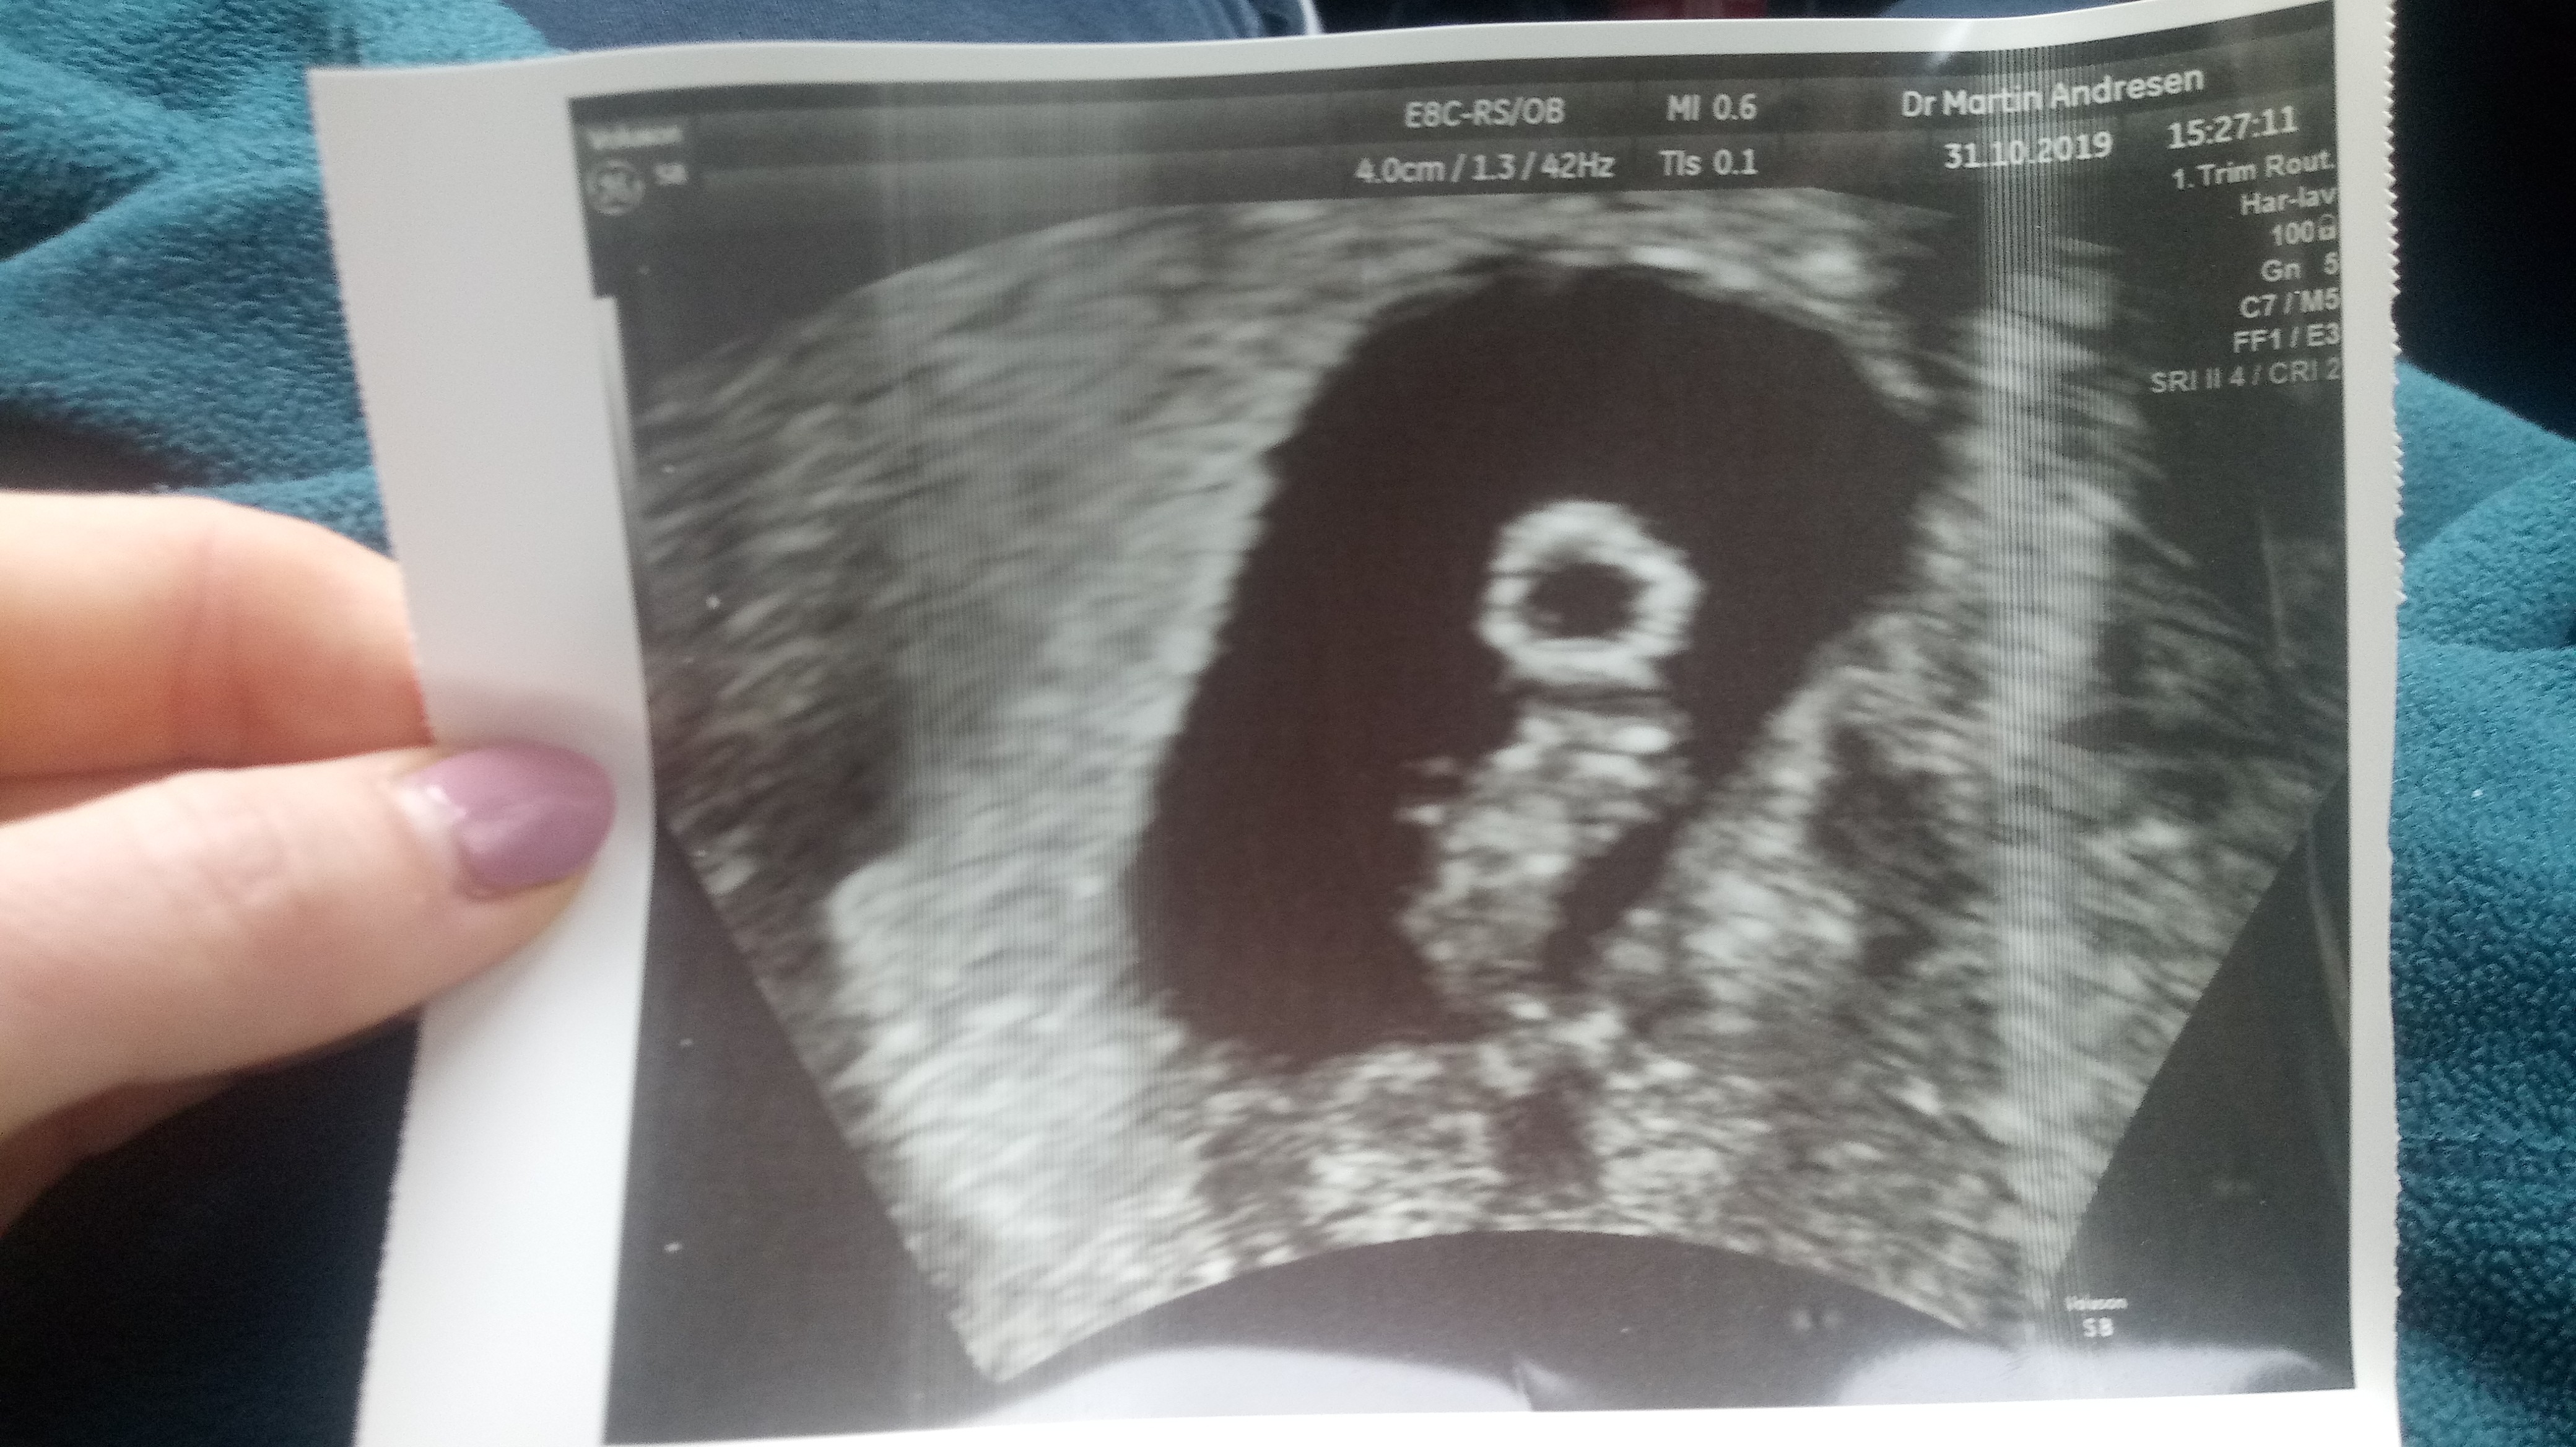

Ja juz po wizycie ☺ jejku ile stresu, moj maz zawalu dostal jak doktor powiedzial: JEST SERCE. A maz dla potwierdzenia: To znaczy, ze dziecko zyje? ❤

Krwawienie bylo z szyjki, podobno niegrozne i juz sie skonczylo. Dostalismy zakaz zblizen

W poniedzialek dzidzia miala 6mm, a dzisiaj juz 10. Z usg 6+6, tak jak z aplikacji. Jaka ulga. Ze tez musialo sie cos takiego wydarzyc... Oby to nie doprowadziło do zadnej infekcji itd.

A oto Gwiazda:

Brawo! Prawdziwa gwiazda! Śliczne zdjęcie![emoji3531][emoji3531][emoji3531]